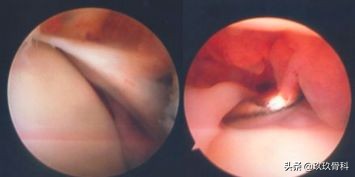

1950 WOLIN首先描述踝关节内半月板样损伤。1991 ANDREWS确认上述损伤是因距腓前韧带撕裂后断端嵌入踝关节前外侧沟中形成,并报告切除这种损伤可缓解踝关节肿痛。

1991 FERKEL通过组织病理学分析证明其为增厚的滑膜组织。从此开始将踝关节无骨折脱位的长期肿痛称为踝关节软组织撞击综合征。

- 前外侧撞击综合征

- 前内侧撞击综合征

统称为踝关节软组织撞击综合征

- 踝前撞击综合征

以上三者统称为踝关节前方撞击综合征

体征:前内或前外间隙压痛;部分病人关节肿痛、背伸受限、不能下蹲。

诊断:踝关节扭伤史、X线无明显异常、踝前疼痛肿胀、经休息及非手术治疗不明显者应考虑为本病。

治疗:踝关节封闭—控制炎症;踝关节镜手术效果较好。